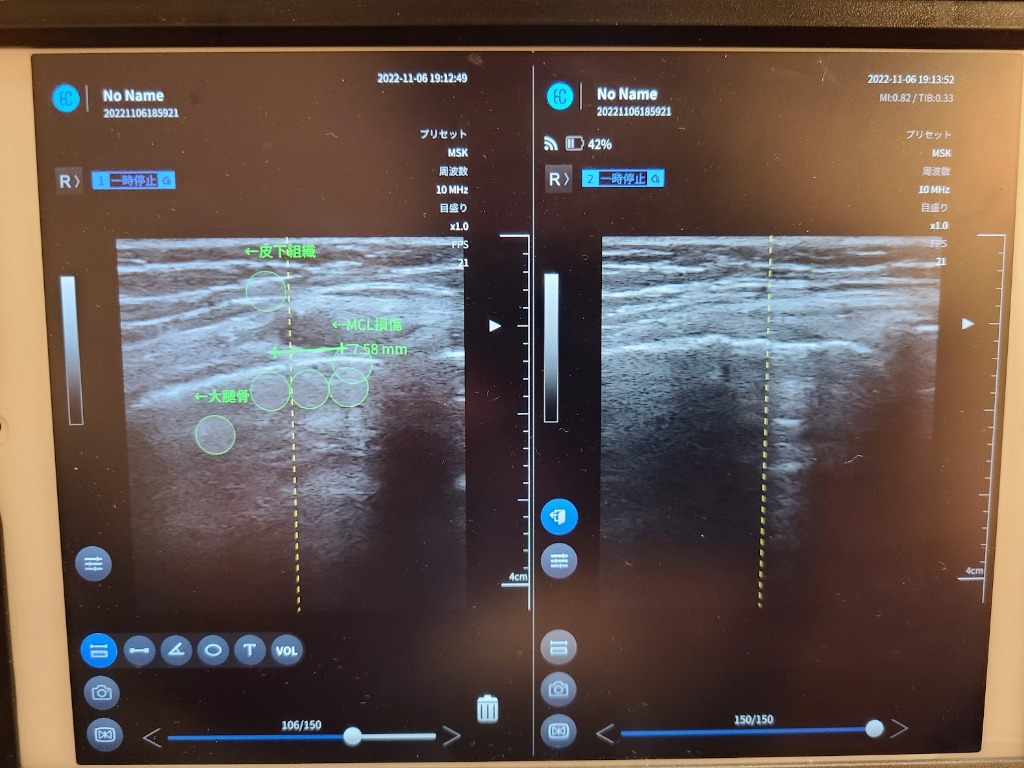

MCL(内側側副靭帯)損傷